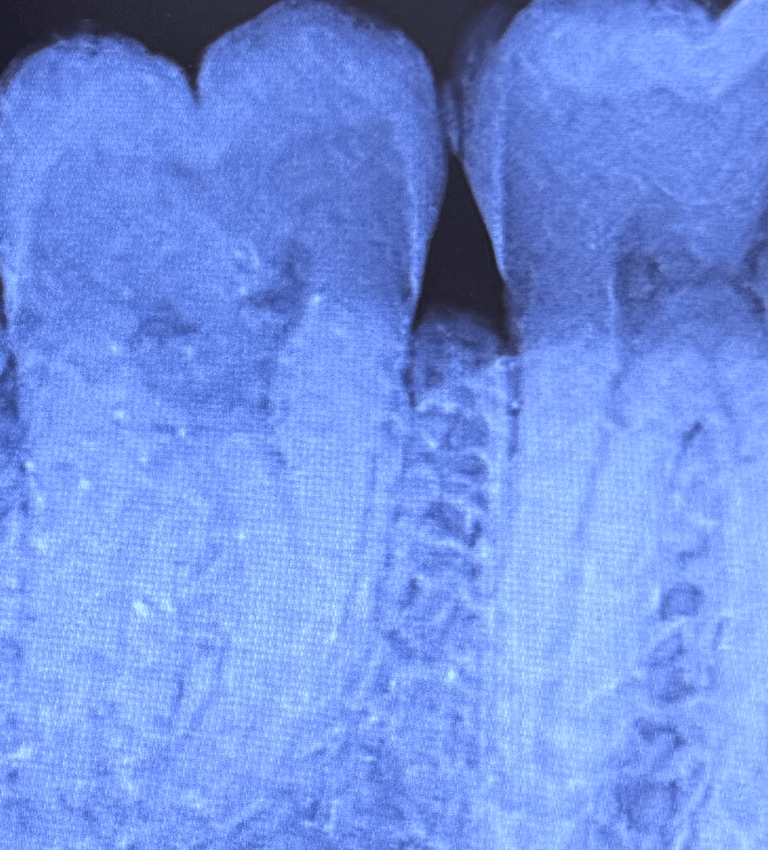

La radiografia endorale è un esame diagnostico che consente di ottenere un’immagine dettagliata di uno o più denti (fino a tre). Si tratta di una procedura minimamente invasiva, sicura e priva di rischi per il paziente.

Questa tecnica viene impiegata per l’analisi mirata di un dente o di un gruppo ristretto di denti, risultando fondamentale per una diagnosi accurata e per il monitoraggio dell’efficacia del trattamento. L’esame si avvale di pellicole o sensori digitali posizionati all’interno del cavo orale e mantenuti in sede da appositi centratori.

Status endorale